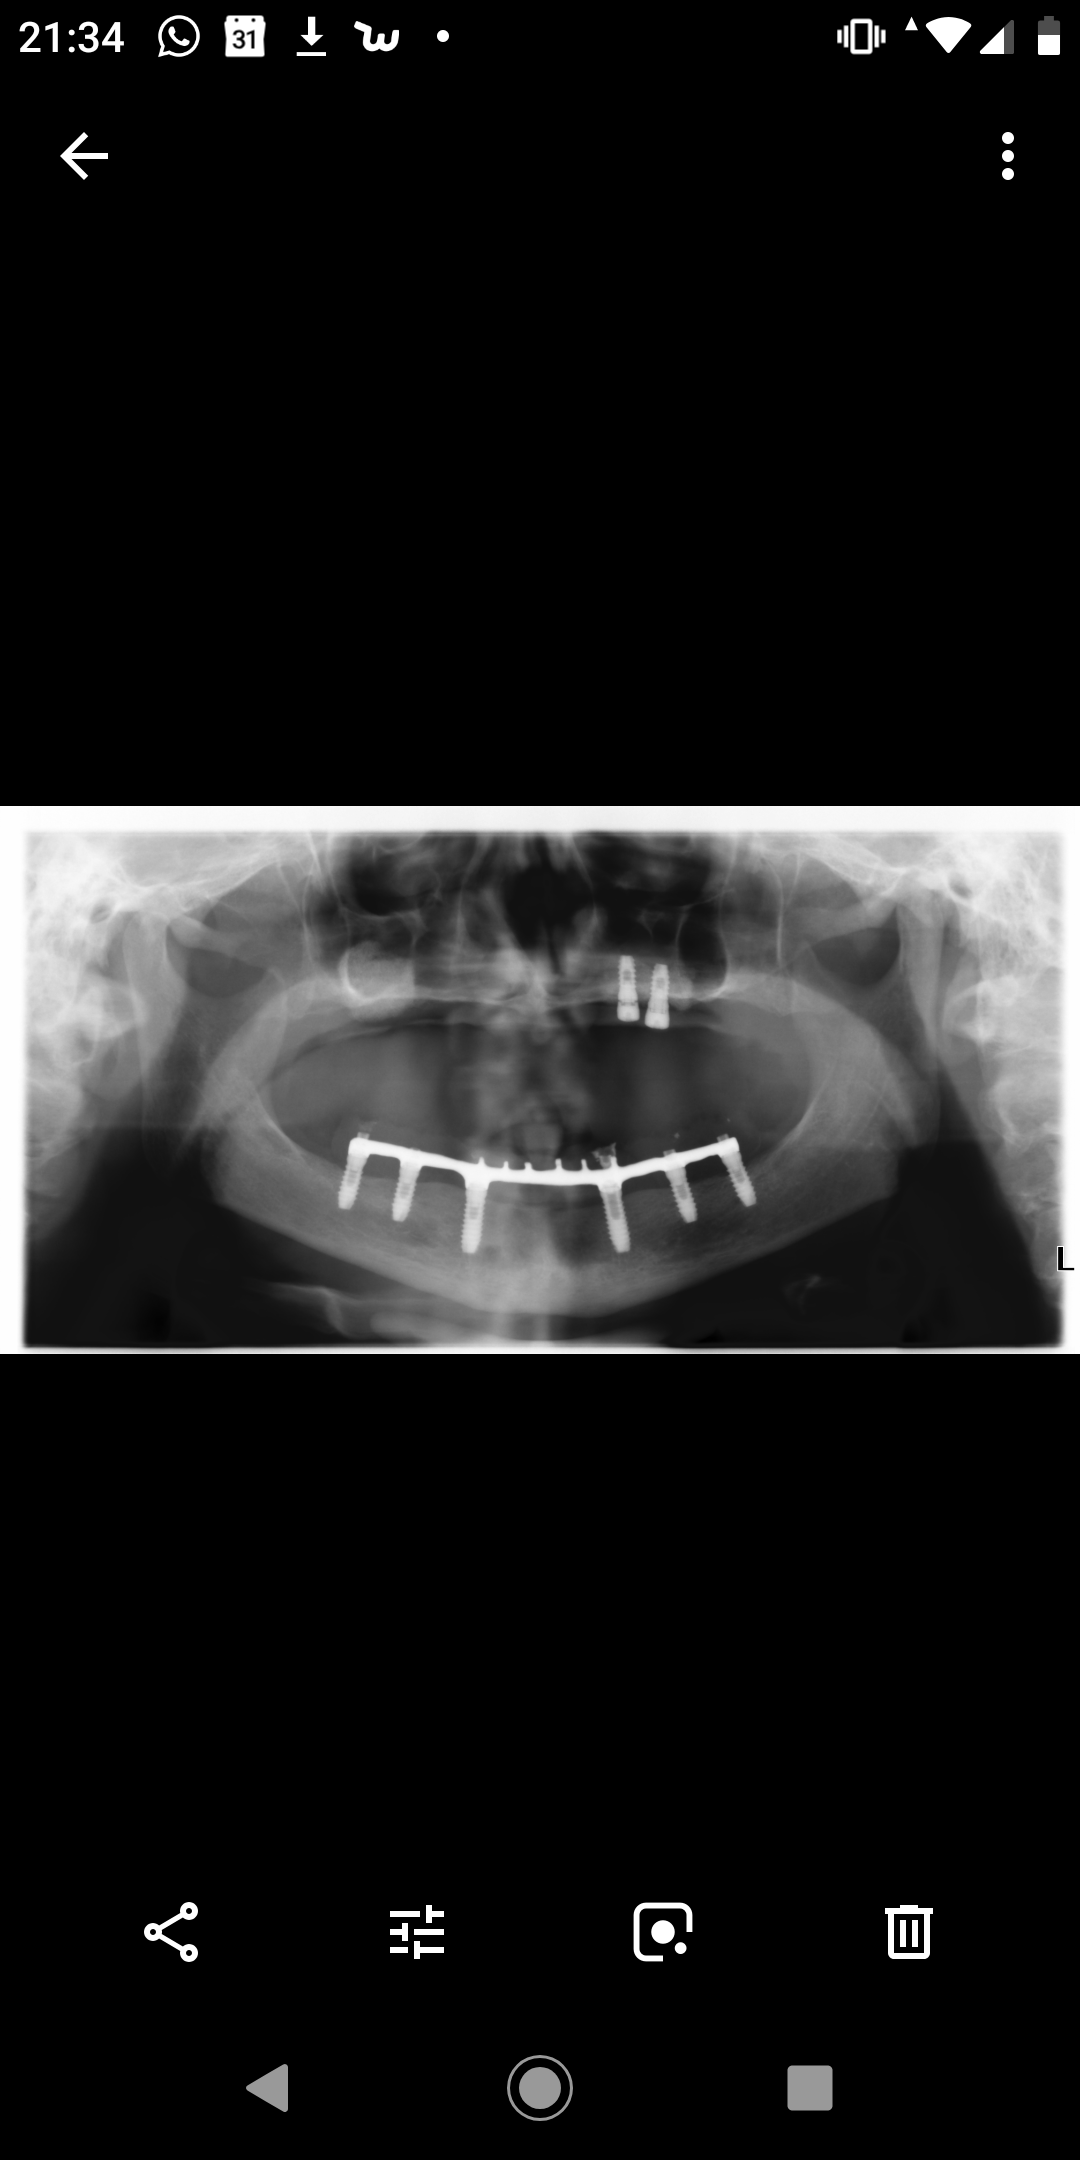

Buenas noches colegas!! Me podriaip ayudar con este caso? Necesitaría saber que implantes lleva esta paciente. Gracias!!

BUENAS TARDES, VAMOS A CAMBIAR LAS CORONAS DE ESTA PACIENTE Y ELLA NO SABE QUE IMPLANTES LLEVA COLOCADOS.